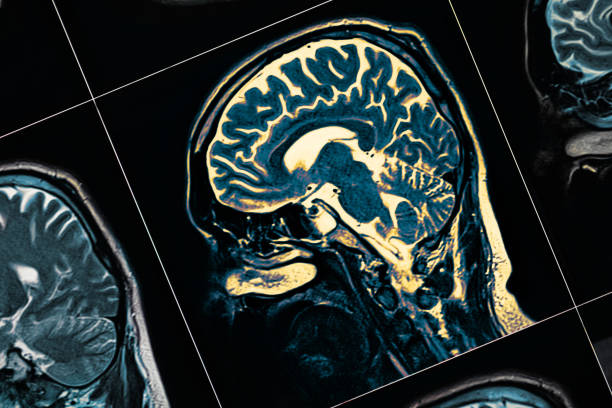

其他专家将参与为您的孩子进行全面的体检、 血液检查、心理健康测试、大脑成像测试和其他检查。它们都是找到正确诊断并制定治疗计划以帮助您的孩子控制疾病的关键。